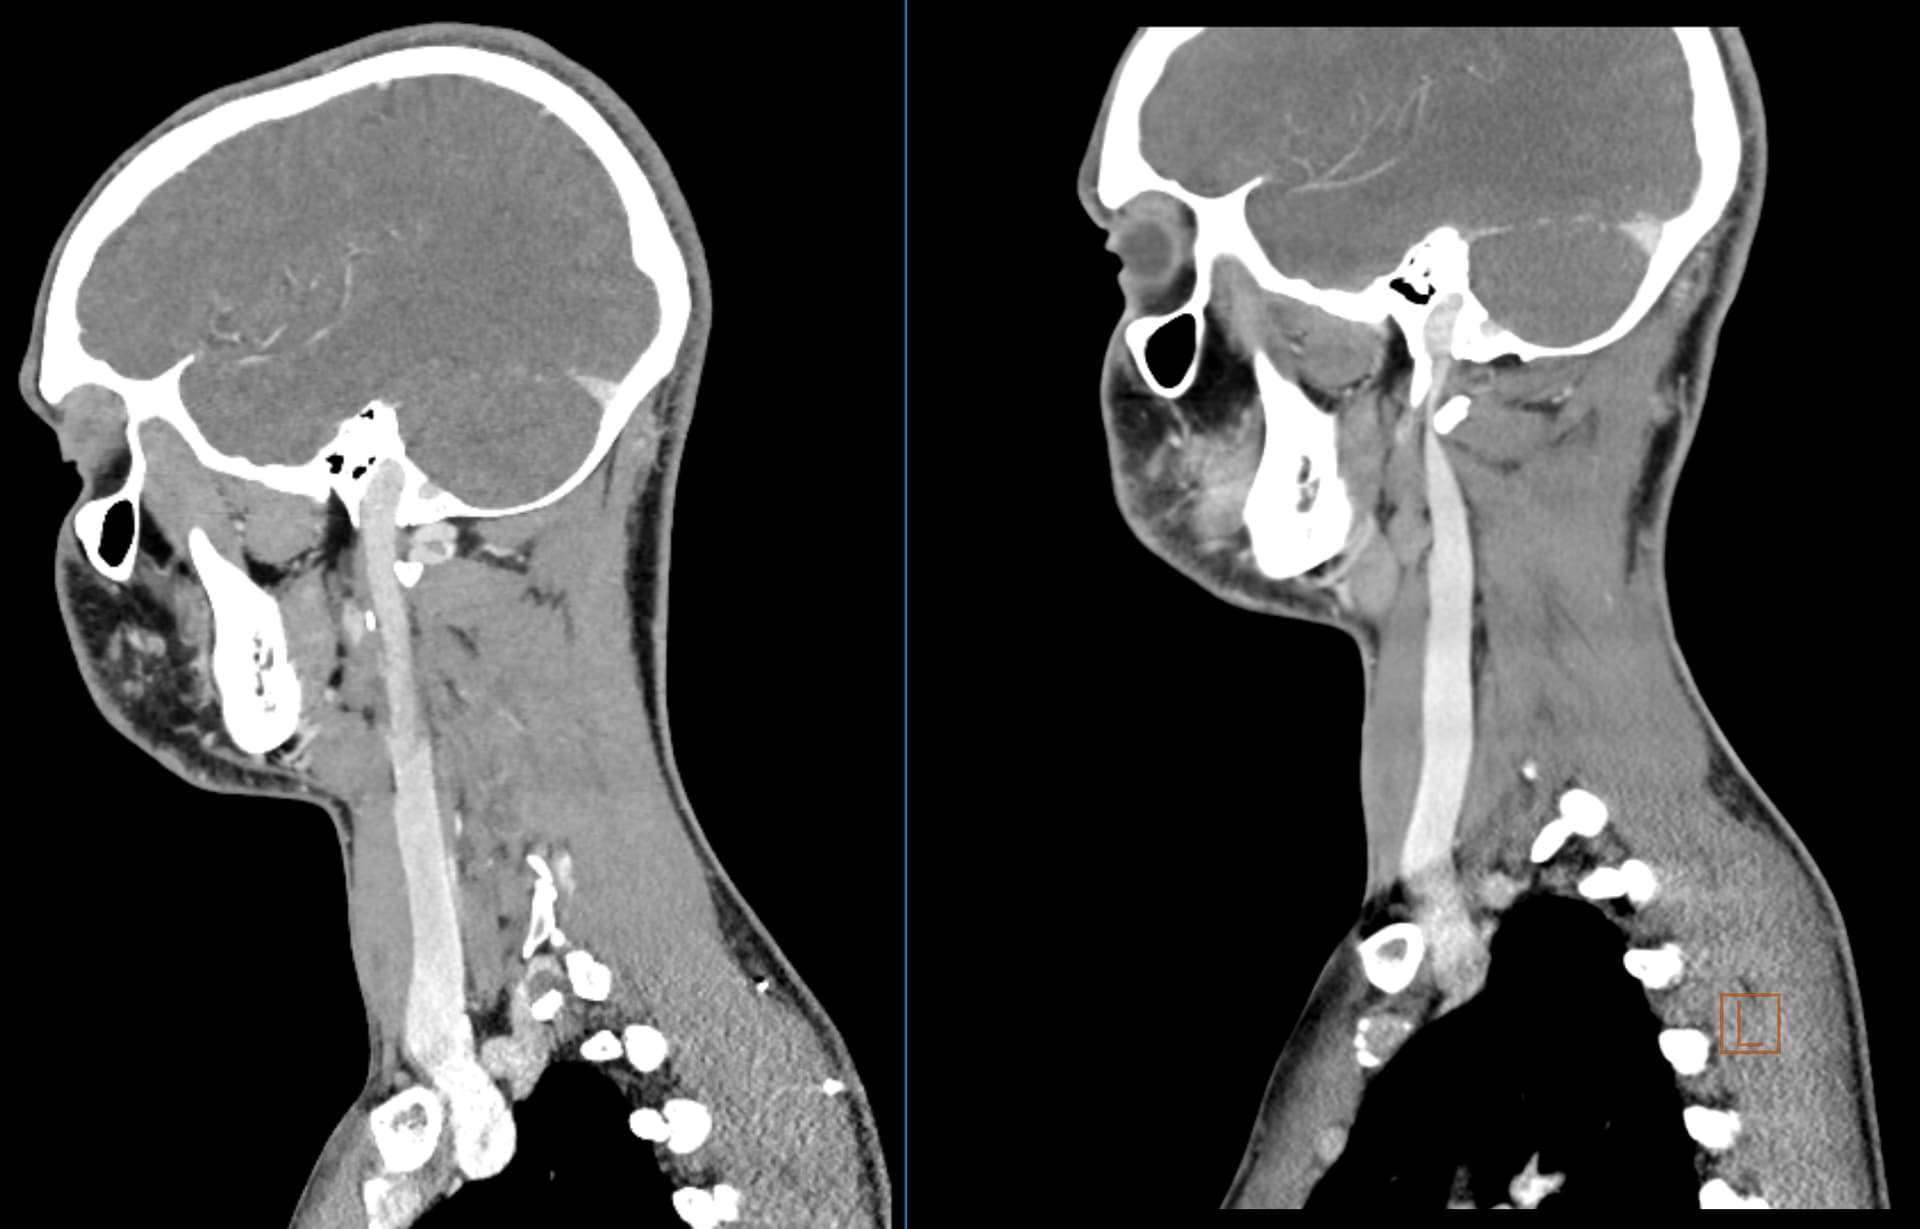

@Isaiah_40_31 @Jules Post-op imaging from today! Left side is post-op, right side is pre-op. Both are of the R IJV. Looks like a tiny bit of residual compression from C1 in some of the slices, but overall looks very open. My biggest concern was scar tissue so no real sign of other compressions is good news! Happy to hear thoughts on it if you guys have them as well

WOW! That’s a significant gain in IJV diameter, @dreamliner. I suspect having the other side done, too will make a more significant difference.